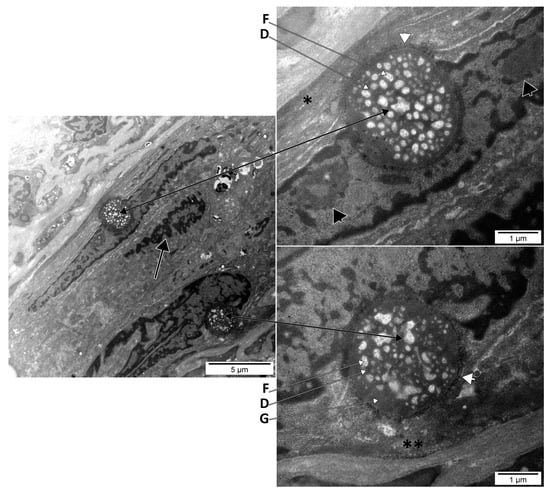

Extruded Nucleoli of Human Dental Pulp Cells

3. Results

4.2. Intracytoplasmic Extruded Nuclear Chromatin and Nucleoli